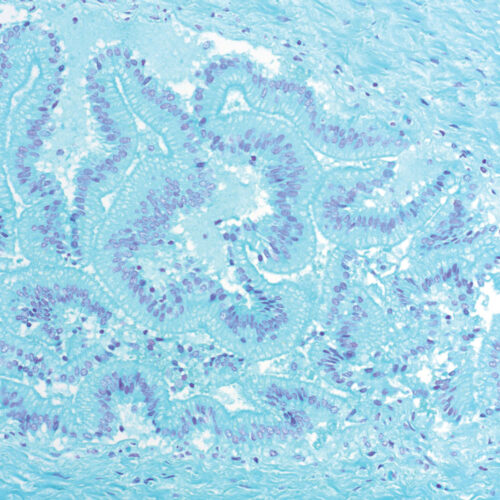

Giemsa HP kit

Four-reagent kit for staining Helicobacter pylori in gastroscopic sections according to Lennart. Advantages of this method for detecting H. pylori are sensitive and reproducible results and easy performance.